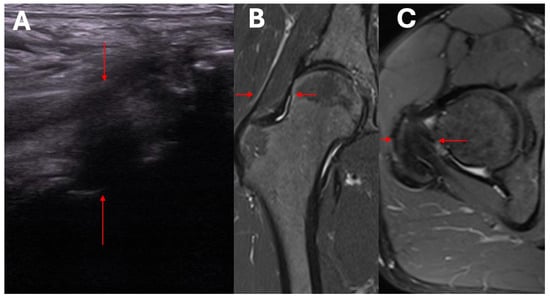

- Ultrasound assessment of hip morphology, and radiologic imaging with MRI where necessary.

- Clinical and ultrasound assessment to identify local pathological mechanisms underlying symptomatic HOA.

- Exclusion/confirmation of intracapsular and extracapsular inflammation based on ultrasound imaging.

- Clinical and ultrasound assessment of the intracapsular, extracapsular, anterior, anteromedial, lateral, and posterolateral aspect of the hip.

- Assessment of capsular adhesion thickness—ultrasonographic evaluation was performed with the probe positioned transversely, allowing for precise visualization of adhesions. The most common location of adhesions was in the anterolateral complex, with less frequent occurrences in the medial complex.